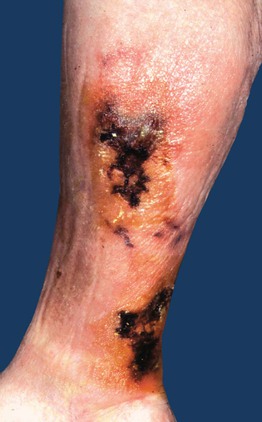

• DDx: early phase of erythema ab igne; viral exanthems (e.g. erythema infectiosum), retiform purpura and necrosis due to more complete disruption of blood flow (Fig. 87.3; see Chapter 18); underlying etiologies are outlined in Table 87.1.

Fig. 87.3 Reticulated purpura and necrosis due to calciphylaxis. These patients can also have patchy areas of livedo reticularis. Courtesy, Norbert Sepp, MD.